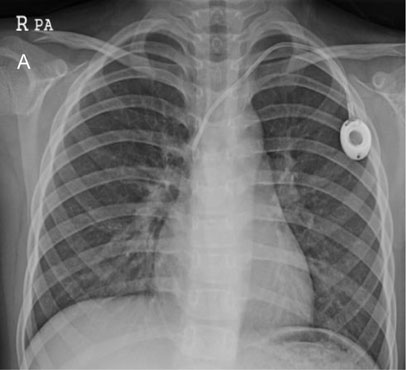

Fig. 1-C

Incomplete removed TIVD

Fig. 1-C Incomplete removed TIVD